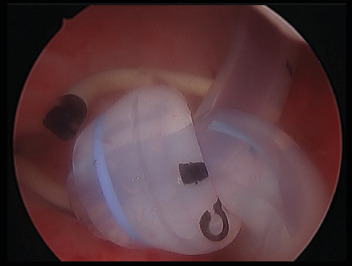

目的:膀胱内自发打结是一种罕见的导尿管并发症。我们提出了一种新的内窥镜治疗方法来处理输尿管支架周围自发打结的导尿管。主题:一名79岁男性因意识不清和急性肾衰竭来到急诊科。他的背景是转移性去势抵抗性前列腺癌。他的相关梗阻性尿路病变通过长期右侧7-Fr r输尿管支架治疗,最后一次更换是在1个月前,并长期18-Fr留置导尿管。CT静脉肾盂造影清楚地显示他的留置导管缠结并穿过右输尿管支架的远端膀胱部分。结果:经皮肾造口术对左肾进行减压后,在透视下尝试用各种导线和导尿管拔出尿管。患者随后接受全身麻醉,并用Mauermayer石粉碎机通过25-Fr通路鞘成功地将结部分去除。结论:内窥镜技术,如使用石粉碎机可能有利于去除困难和复杂的导管结,正如本病例所示。导管打结应始终考虑,如果功能或试图去除导管是异常的,并及时转诊到泌尿科医生。

Objective: Spontaneous intravesical knotting is a highly infrequent complication of urinary catheters. We present a novel endoscopic treatment approach to managing a spontaneously knotted urinary catheter around a ureteric stent. Subject: A 79-year-old man presented to the Emergency department with confusion and acute renal failure. His background was significant for metastatic castrate-resistant prostate cancer. His associated obstructive uropathy was managed with a long-term right 7-Fr Rüsch ureteric stent, last changed 1 month prior and a long-term 18-Fr indwelling catheter. A CT intravenous pyelogram clearly demonstrated his indwelling catheter knotted around and through the distal intravesical portion of an appropriately positioned right ureteric stent. Results: Following decompression of the left kidney via percutaneous nephrostomy, attempts were made to remove the urinary catheter under fluoroscopy with a variety of wires and introducers. The patient then underwent a general anesthesia, and the knot was successfully removed piecemeal with a Mauermayer stone crusher via 25-Fr access sheath. Conclusion: Endoscopic techniques such as the use of a stone crusher may be beneficial for the removal of difficult and complex catheter knots as demonstrated in this case. Catheter knotting should always be considered if the functioning or attempted removal of the catheter is abnormal and timely referral to a urologist is made.